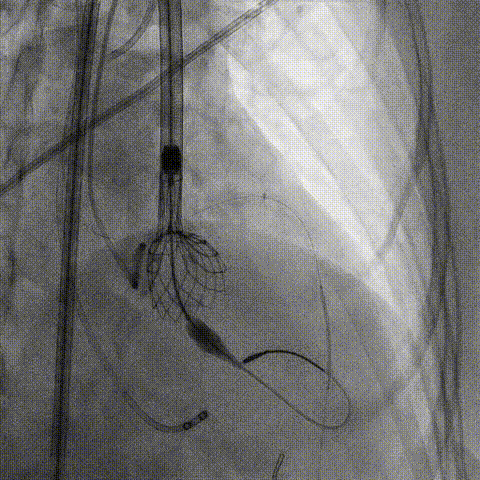

调整支架位置

释放冠脉支架

释放瓣膜

造影评估

支架内后扩张

冠脉造影

根部造影

最终结果